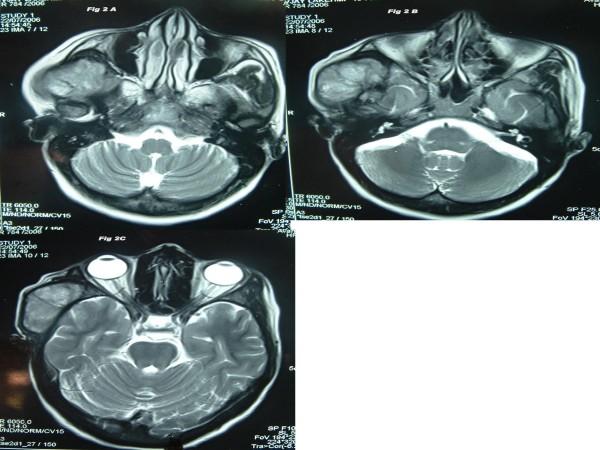

We present a case of a 41-year-old female that presented with swelling in the right preauricular region that had persisted for the past two years. The patient was diagnosed as having a small lymphocytic NHL. She initially underwent chemo-radiation but reported relapse. The tumor was excised and again the patient underwent chemotherapy. The patient remained symptomatic and developed a second primary squamous cell carcinoma in the right retromolar trigone.

我们报告一例41岁女性患者,其右耳前区肿胀持续两年。该患者被诊断为小淋巴细胞性NHL。她最初接受了放化疗,但出现复发。肿瘤被切除,患者再次接受化疗。患者仍有症状,并在右磨牙后三角区发生了第二原发性鳞状细胞癌。